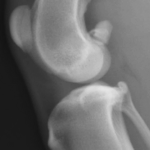

With time, arthritis sets in. Arthritic change includes new bone formation around the joint, called osteophytosis (asterisks).

The knee on the left has a patellar luxation. The knee on the right is normal.